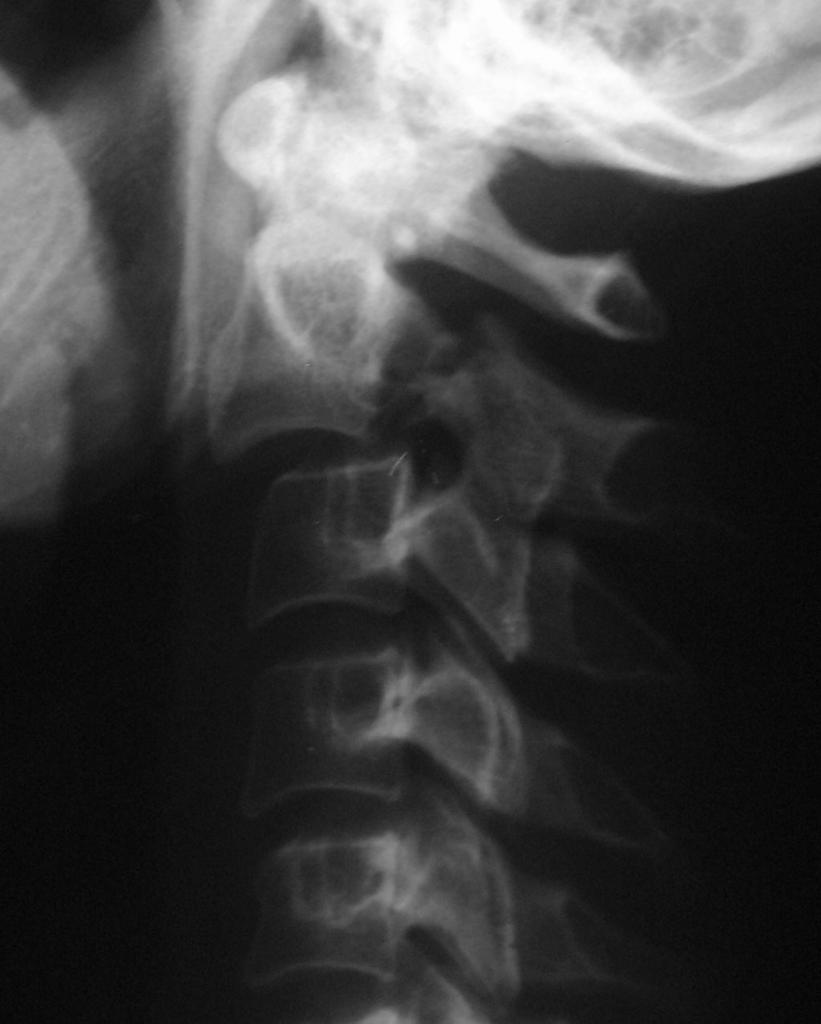

C-spine Radiographs

• By 8 to 9 years of age, cervical spine reaches adult proportions

• Cervical spine injuries in children usually occur high - from the occiput to C3 vertebra

• Fulcrum of motion in children is at the C2-C3 level rather than at the C5-C6 level in adults

• Owing to hypermobility of the c-spine because of ligamentous laxity, shallow and angled facet joints, anteriorly wedged vertebrae, and underdeveloped spinous processes

• Weak neck muscles, underdeveloped odontoid process, and large head also contribute to instability of the c-spine

Approach

• Every lateral c-spine view should visualize at least the top of T1, of not, may need swimmer’s

• Lateral

• Upper C-spine

• Atlantodens interval (< 5 mm)

• Spinolaminar line should intersect with opisthion

• Relationship between basion and odontoid and posterior vertebral line for atlantooccipital dislocation - should be less than 12 mm (?), head usually dislocated anterior on cervical spine

• Look at odontoid

• C2 on C3 subluxation, C2 pedicles

• Lower C-spine

• Anterior vertebral body line

• Posterior vertebral body line

• Articular pillars

• Spinolaminar line

• Disc spaces should be roughly equal

• Interspinous spaces should be uniform

• Kyphotic deformity

• Prevertebral tissues (see below)